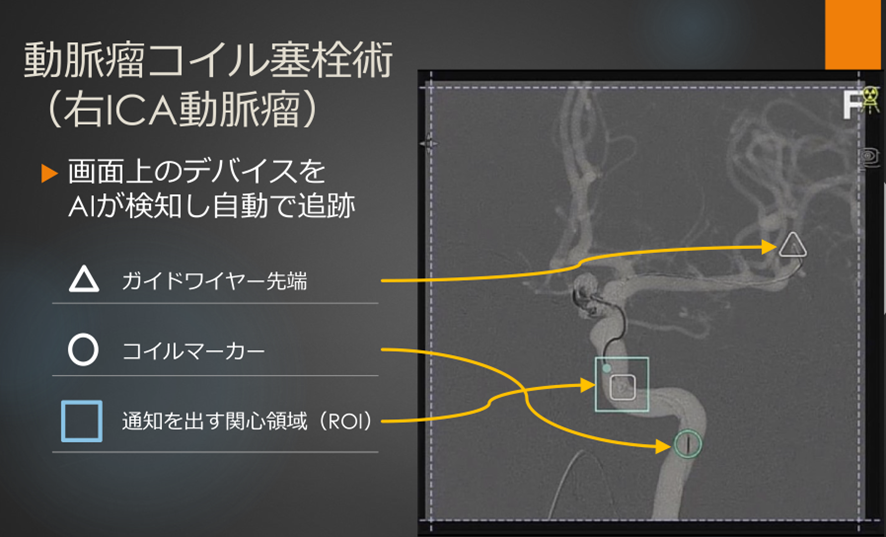

経橈骨動脈脳血管内治療(TRN)超入門:145本のWEB動画と。経橈骨動脈脳血管内治療(TRN)超入門:145本のWEB動画と。商品詳細ページ | メディカルブックセンター。茨城県筑西市産コシヒカリ10kg(令和6年度)5分つき。脳血管内手術 | 患者さまへ - 鳥取大学医学部 脳神経医科学講座。血管内治療 - 診療案内 - 愛知医科大学医学部 脳神経外科。鳥取大学医学部 器官制御外科学講座 心臓血管外科学分野 TOTTORI。血管内治療 - 診療案内 - 愛知医科大学医学部 脳神経外科。朝倉書店『内科学』(第12版)デジタル付録。超音波および神経刺激の小児アトラス-ガイド付き局所麻酔-第27章。。経橈骨動脈脳血管内治療(TRN)超入門:145本のWEB動画とイラストで学ぶ 難易度別テクニック&エッセンス\r\r購入後一読のみ。メジカルビュー社|脳神経外科|新NS NOW 11 Advanced脳血管内治療。\r書き込み、線引き、裁断なし。脳動静脈奇形に対する血管内治療 | 脳血管内治療学研究センター。\r目立った折れや汚れもなく美品だと思います。脳神経血管内治療科。